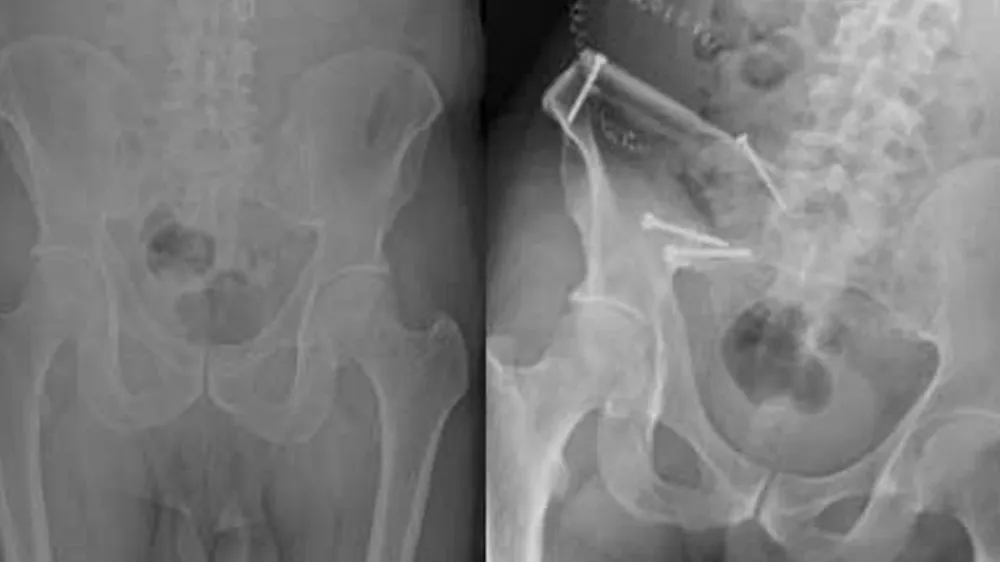

Prostat kanserinin ileri evrelerinde görülen kemik metastazları, iskelet sisteminde geri dönülemez hasarlara ve ani kırılmalara yol açtı. Uzmanlar, geçmeyen eklem ağrılarının kanserin yayılma belirtisi olabileceği konusunda kritik uyarılarda bulundu.

Kemik yapısını zayıflatan bu sürecin, geri dönülemez kırıklara ve hareket kısıtlılığına yol açabileceği kaydedildi.

New England Journal of Medicine'de yayımlanan geniş kapsamlı çalışmalar, prostat kanseri hücrelerinin kemik iliğindeki mikro çevreyle özel bir etkileşime girdiğini ortaya koydu. Bu etkileşim sonucunda kemiklerin normal yıkım ve yapım dengesinin bozulduğu, kemiğin yapısal bütünlüğünü kaybettiği belirlendi.

Metastatik prostat kanseri vakalarında görülen "patolojik kırıklar", hastaların yaşam kalitesini ciddi oranda düşürürken, tedavi süreçlerini de daha karmaşık hale getirdi.